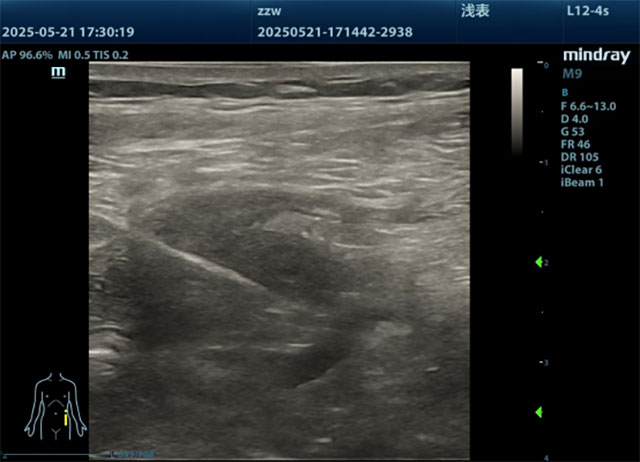

治疗第一步,团队先用中药汤剂为赵先生调理身体,同时外敷药方缓解疼痛,为放疗做好准备。到了插植放疗当天,麻醉师给药后,赵先生很快进入睡眠状态。张燕副教授在彩超引导下,仅用3分钟就将插植针精准插入肿瘤组织——这一步就像为射线“搭建瞄准镜”,让放疗能量能集中作用于病灶。